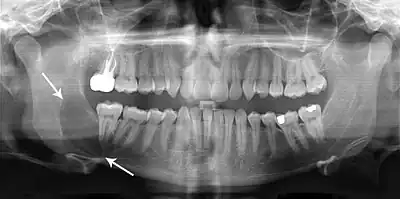

Classic look of an odontogenic keratocyst of the right mandible in the place of a former wisdom tooth. Well defined, unilocular, radiolucent lesion within the bone.

Radiographs of odontogenic keratocysts show well-defined radiolucent areas with rounded or scalloped margins which are well demarcated.[13] These areas can be multilocular or unilocular. The growth pattern of the lesion is very characteristic from which a diagnosis can be made as there is growth and spread both forward and backward along the medullary cavity with little expansion. No resorption of teeth or inferior dental canal and minimal displacement of teeth is seen. Due to lack of expansion of the odontogenic keratocyst, the lesion can be very large when radiographically discovered.[10]